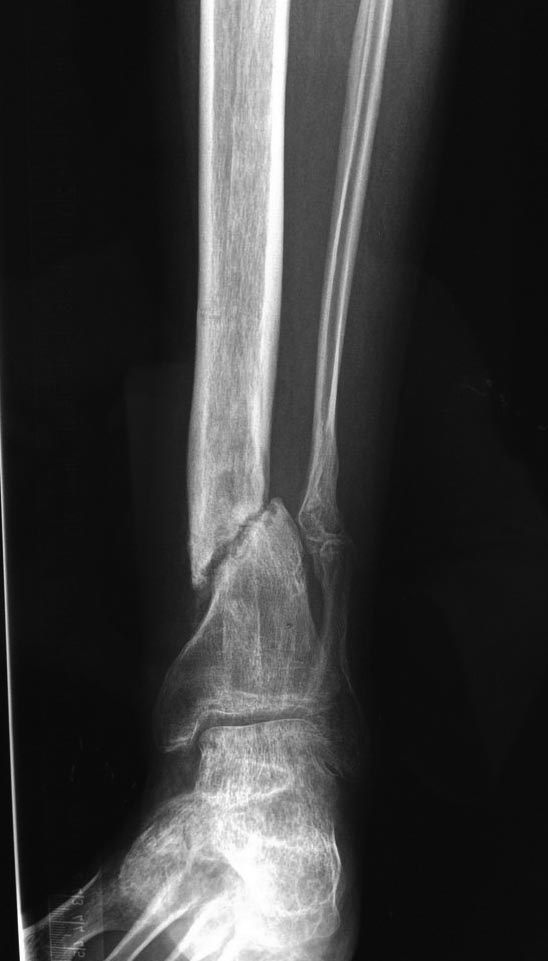

Через 6 мес. контроль - линия ложного сустава прослеживается, но имеется

периостальная костная мозоль.

Не хватает стабильности.

Вопрос что делать?